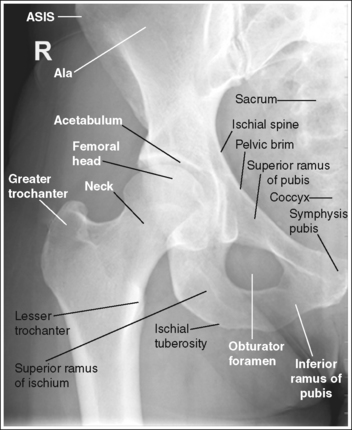

Hip: Anteroposterior Oblique Projection (Modified Cleaves Method)

See Figure 7-8 and Box 7-3.

The pelvis demonstrates an AP projection. The ischial spine is aligned with the pelvic brim, the sacrum and coccyx are aligned with the symphysis pubis, and the obturator foramen is open.

• An AP oblique projection of the hip is obtained by placing the patient supine on the imaging table, with the unaffected leg extended and the affected leg flexed and abducted (Figure 7-9). To ensure that the pelvis is not rotated, judge the distances from the ASISs to the imaging table. The distance on each side should be equal.

• Detecting pelvis rotation. Rotation of the pelvis on an AP oblique projection is detected by evaluating the relationship of the ischial spine and the pelvic brim, the alignment of the sacrum and coccyx with the symphysis pubis, and the demonstration of the obturator foramen. If the patient was rotated toward the affected hip, the ischial spine is demonstrated without pelvic brim superimposition, the sacrum and coccyx are not aligned with the symphysis pubis but are rotated away from the affected hip, and demonstration of the obturator foramen is decreased (see Image 6). If the patient was rotated away from the affected hip, the ischial spine is not aligned with the pelvic brim but is demonstrated closer to the acetabulum, the sacrum and coccyx are not aligned with the symphysis pubis but are rotated toward the affected hip, and demonstration of the obturator foramen is increased (see Image 7).

The lesser trochanter is in profile medially, and the femoral neck is superimposed over the greater trochanter.

• Accurate femur positioning. To position the greater trochanter accurately beneath the proximal femur and position the lesser trochanter in profile, flex the patient's knee and hip until the femur is angled at 60 to 70 degrees with the imaging table (20 to 30 degrees from vertical) (Figure 7-11).

• Accurate leg positioning. To demonstrate the femoral neck and proximal femur with only partial foreshortening and the proximal greater trochanter at a transverse level halfway between the femoral head and lesser trochanter on an AP oblique hip projection, abduct the femoral shaft to a 45-degree angle from vertical (Figure 7-12).

The femoral neck is at the center of the exposure field. The acetabulum, greater and lesser trochanters, and femoral head and neck, as well as half of the sacrum, coccyx, and symphysis pubis, are included within the collimated field.

• Center a perpendicular central ray 2.5 inches (6.25 cm) distal to the midpoint of a line connecting the ASIS and superior symphysis pubis to center the femoral neck in the center of the exposure field. Center the IR to the central ray and open longitudinal collimation to include the ASIS. Transversely collimate to the patient's midsagittal plane and transversely collimate to within 0.5 inch (1.25 cm) of the lateral hip skin line.

• Including half of the sacrum, coccyx, and symphysis pubis within the exposure field provides a way to evaluate pelvic rotation.